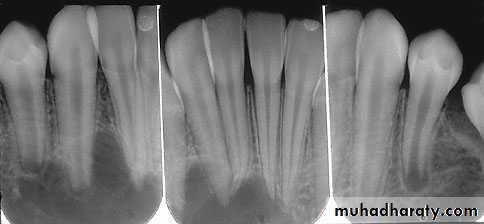

radiographical features

The cavity well circumscribed, rounded and unilocular and contain the crown of a tooth displaced from normal position.

The slow growth of DC result in a seclerotic bony outline and well defined cortex.

Some times shoe pseudo- loculation due to bone trabeculation

• The affected tooth is often displaced to considerable distance and the lower third molar may be pushed to the lower border of the mandible.

* If the cyst remain un-recognised for long period the enclosed tooth may be resorbed.